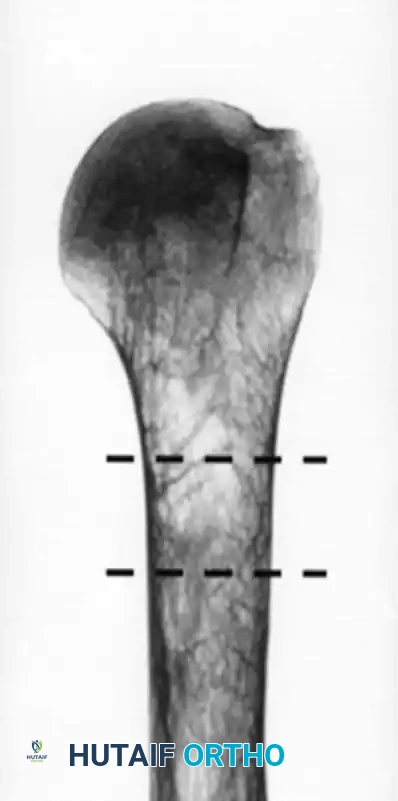

قياس كثافة العظام وسماكة القشرة

تعتبر سماكة قشرة عظمة العضد مؤشراً قوياً على كثافة العظام. إذا كانت العظام هشة جداً وقشرتها رقيقة، فقد لا تتمكن المسامير الطبية من التثبيت فيها بقوة. في هذه الحالات، قد يفضل الجراح استخدام تقنيات بديلة مثل الخياطة العظمية أو اللجوء إلى المفاصل الصناعية بدلاً من الشرائح والمسامير التقليدية.

إليك بعض الصور الإشعاعية والرسوم التوضيحية الإضافية التي توضح أشكال التثبيت الجراحي المختلفة لكسور أعلى عظمة العضد